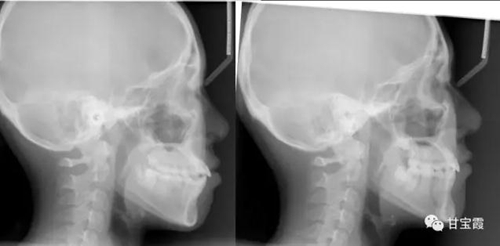

我有個朋友的小女孩前牙不齊、有點突,要求矯正。經(jīng)過臨床檢查和X診斷,發(fā)現(xiàn)先天缺失兩顆下頜第二雙尖牙。

1.jpg

2.jpg